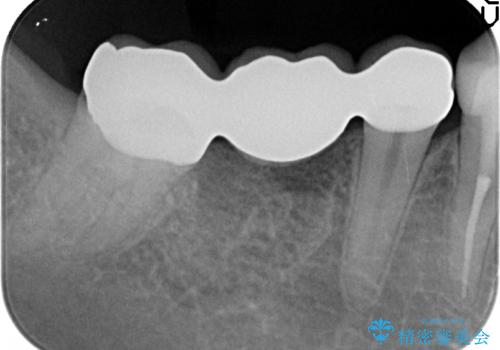

右下の奥歯の虫歯が大きく、やりかえが難しい状態でした。

外して虫歯を取ったところ。歯茎の深いところまで虫歯があり、やむなく抜歯しました。